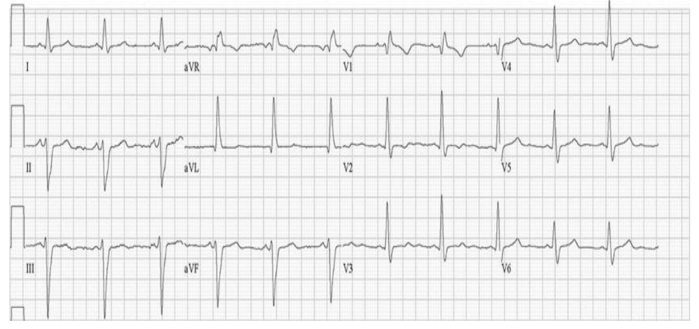

Homem de 32 anos, natural do interior da Bahia, trabalhador rural, relata cansaço progressivo há 6 meses, atualmente aos moderados

esforços, como subir dois lances de escadas. Apresenta também crises de palpitação autolimitadas, com sensação de desmaio, porém sem

episódios de síncope. Nega dor torácica, tabagismo, etilismo ou qualquer outra comorbidade. Desde a infância tem o hábito de tomar

banhos de rio, e residiu em casa de pau a pique até a adolescência. Mãe falecida de cardiopatia aos 58 anos, um irmão falecido

subitamente aos 36 anos.

Exame físico: corado, anictérico, acianótico, eupneico em repouso. Frequência cardíaca: 70 bpm, Pressão arterial: 96x58mmHg, murmúrio

vesicular reduzido na base direita com crepitação em ambos os 1/3 inferiores, turgência jugular patológica, ictus globoso palpável no 5º

espaço intercostal esquerdo, na linha axilar anterior, ritmo cardíaco regular em 3T (B3), bulhas hipofonéticas, sopro sistólico 3+/6+ em foco

mitral com irradiação axilar, aumento do volume abdominal com hepatimetria 14 cm, membros inferiores com edema bilateral até joelhos

2+/4, com cacifo. Pulsos pediosos palpáveis. Ecocardiograma mostrou disfunção sistólica moderada do ventrículo esquerdo (fração de

ejeção 38%) com presença de aneurisma e trombo apicais, e disfunção sistólica leve do ventrículo direito. Eletrocardiograma de admissão

está abaixo.